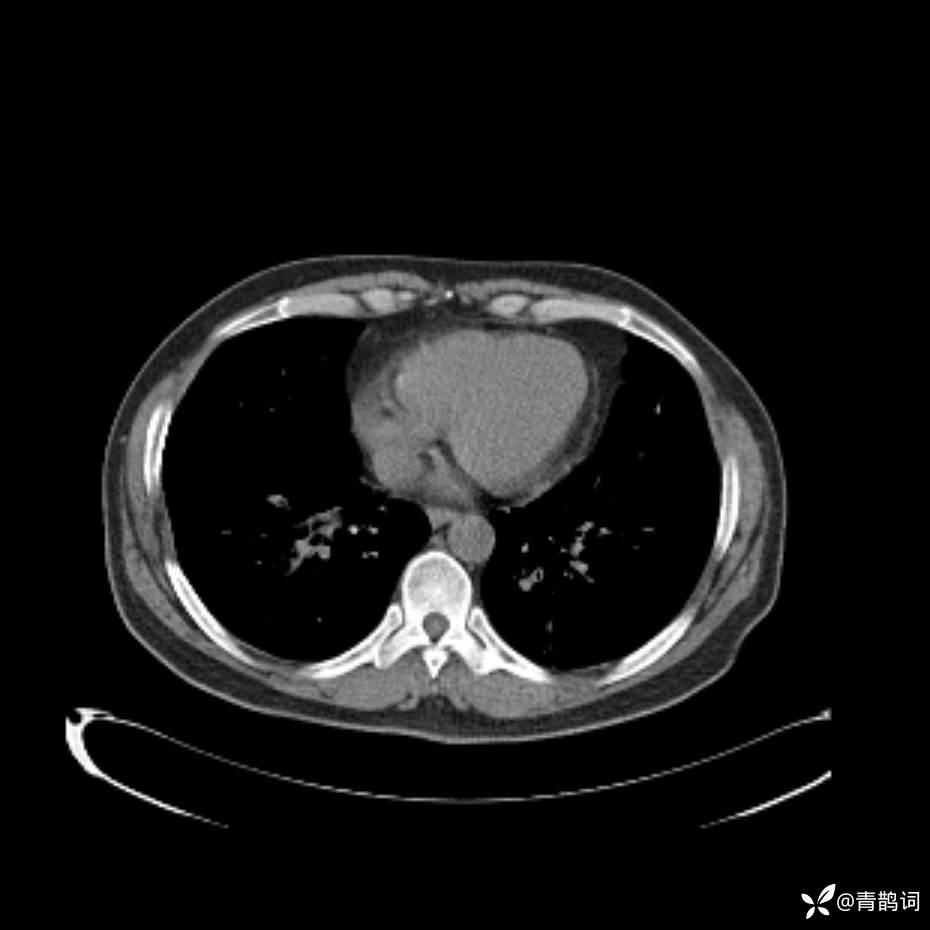

患者年龄:30岁。

患者性别:男。

简要病史:左颜面部肿胀2年,反复咳嗽咳痰,逐渐加重。

辅助检查

结合病史及影像学表现,期待评论区各位老师各抒己见~